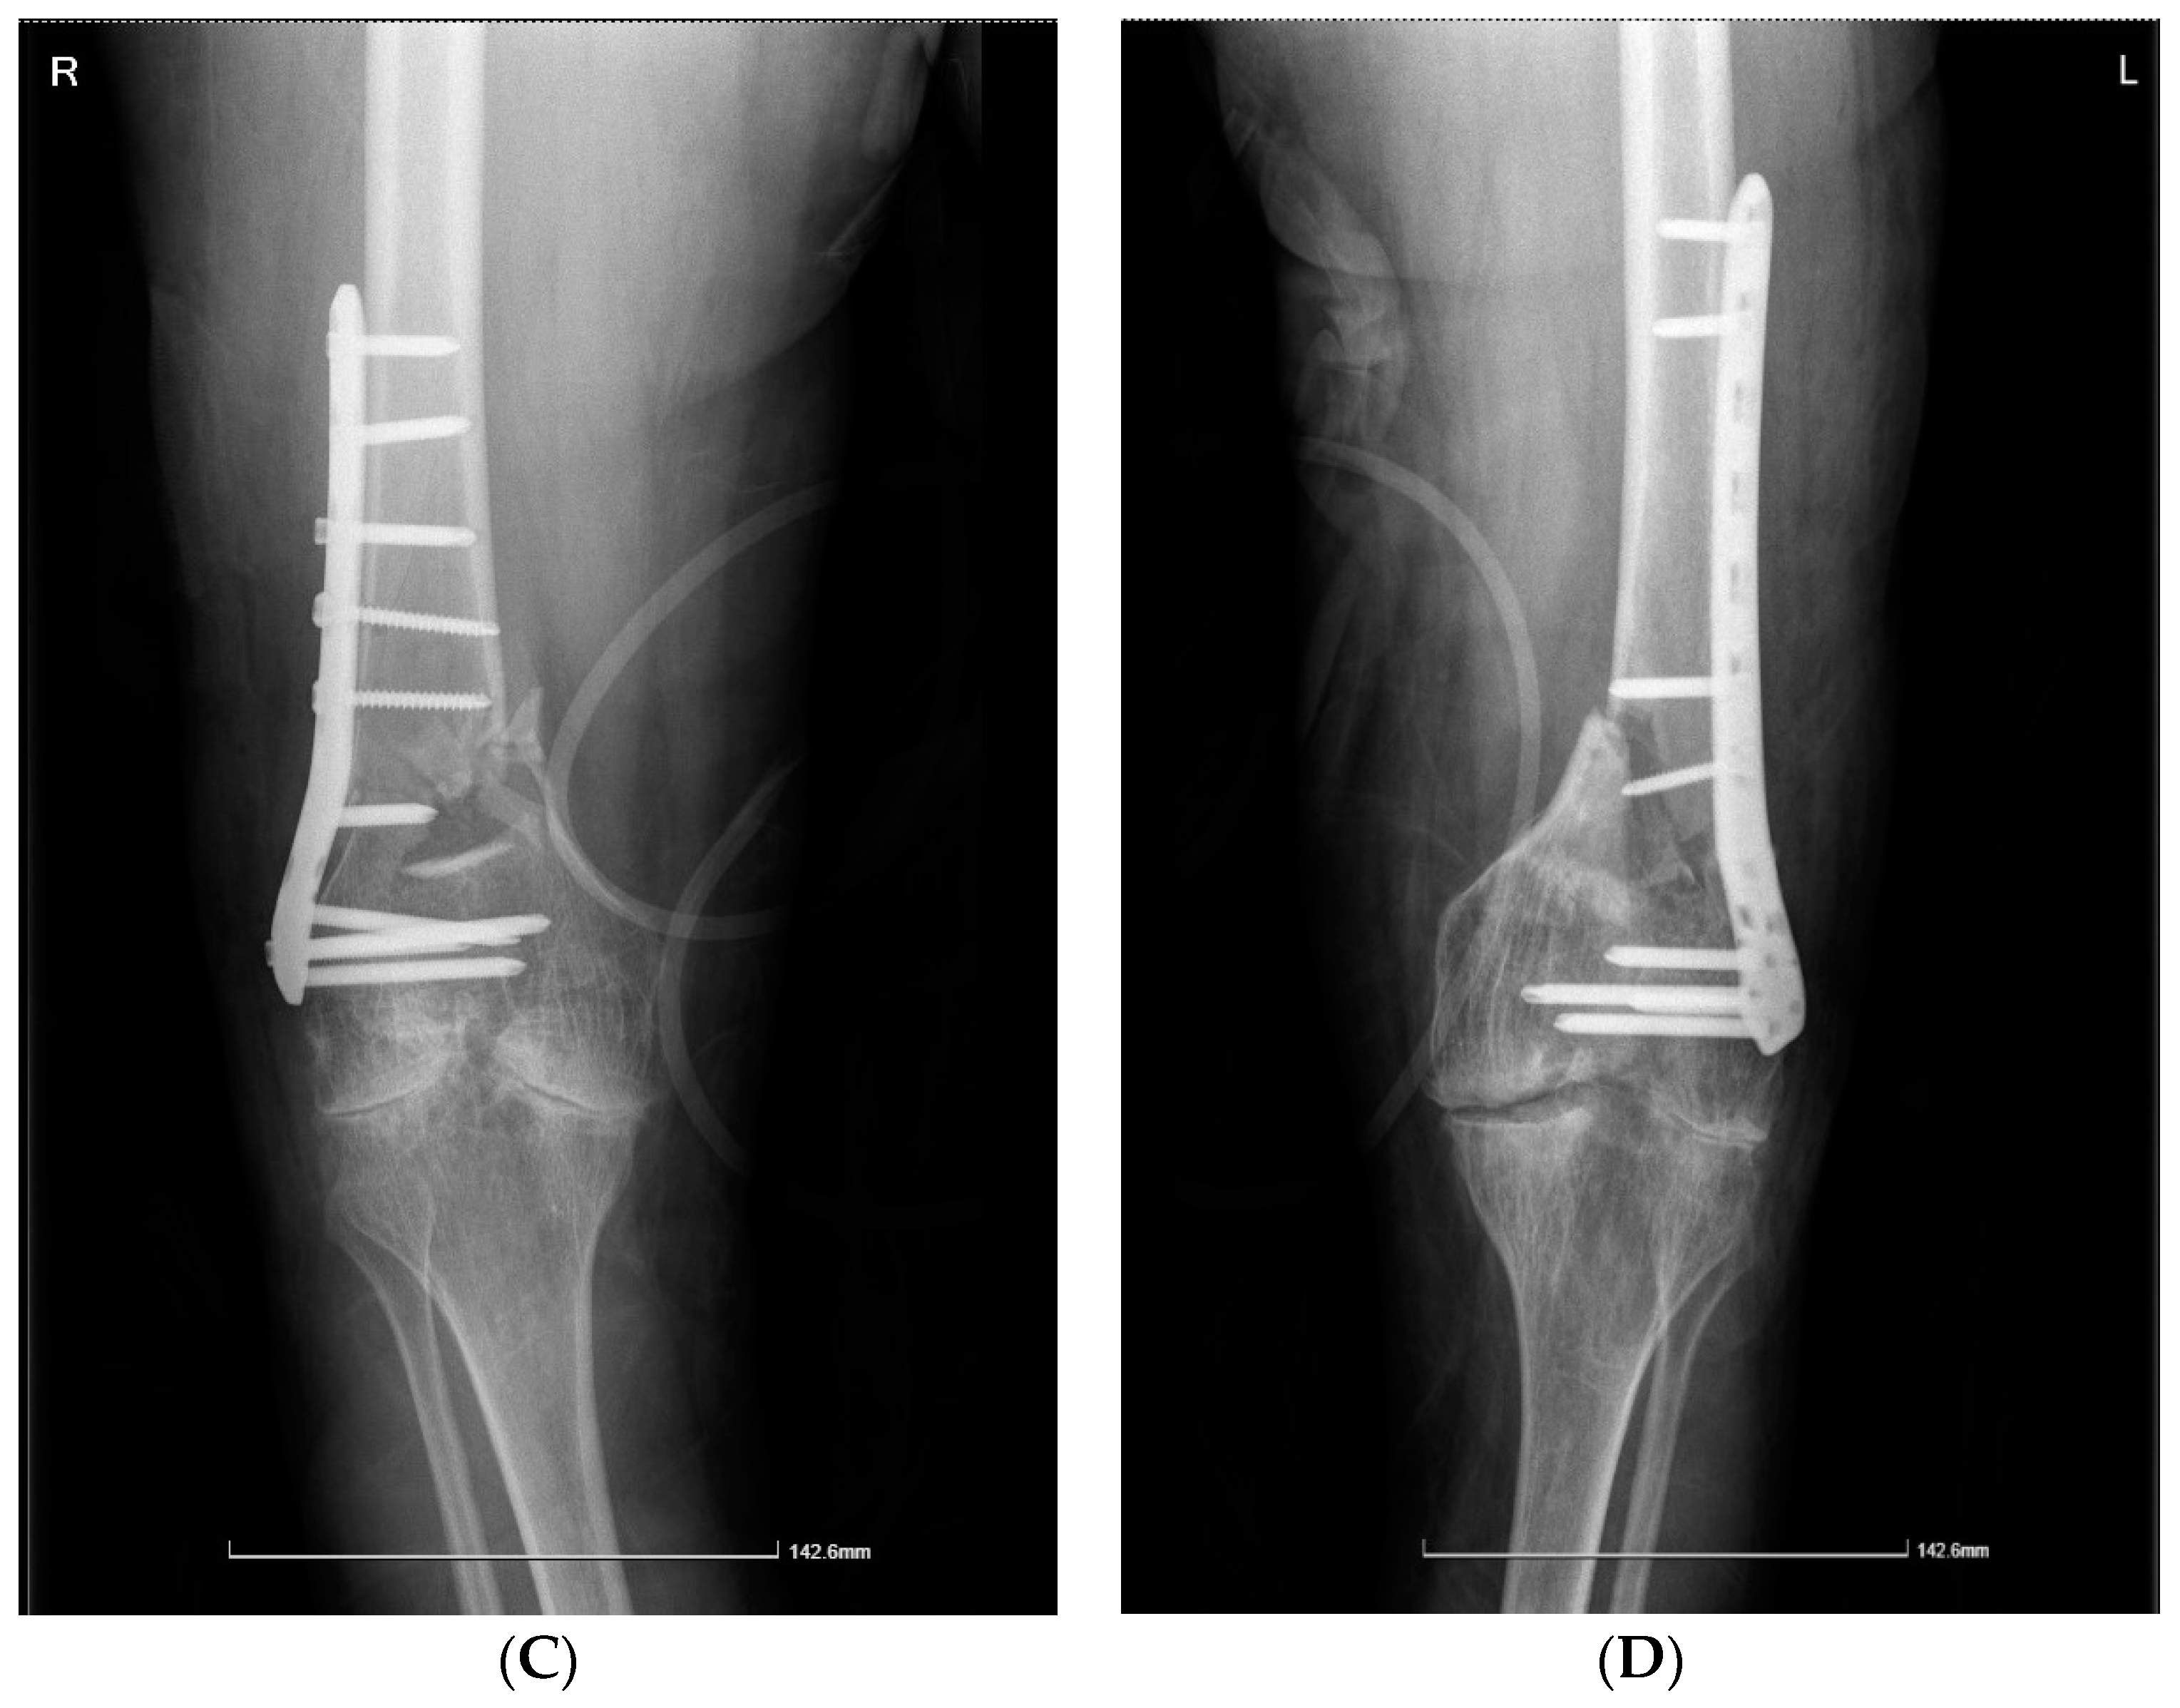

| Case 2. 39-years-old male, with severe haemophilia A | -chronic viral hepatitis C | -post-traumatic bilateral femoral supracondylar fracture | -open reduction and osteosynthesis with plates and screws of the pelvic limb bilaterally | ~1300 mL (4 units pRBCs) | ~40,217.44 € (71.78% for EHL FVIII concentrate) | No | Good, discharge after 21 days |